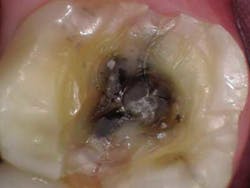

At the crown appointment, the amalgam filling and compromised mesial and distal marginal ridges were removed. The fracture line was indeed detected and noted to extend across the floor in a mesial/distal fashion.Fig. 3

The entire area was cleaned out, a build-up was placed, and the tooth was prepped for a full zirconia crown. At the end of the appointment, the patient was shown the picture of the fracture line and was informed that even though the tooth did not present in an irreversible nature, it still could need a root canal in the unforeseen future.

The endodontist evaluated the tooth and diagnosed the tooth with pulpal necrosis and symptomatic apical periodontitis and recommended RCT. When access was gained, the endodontist observed a necrotic pulp. Staining also showed that the crack line extended across the entire pulpal floor and down the mesial and distal sides of the pulpal cavity. Concerns with this defect included: